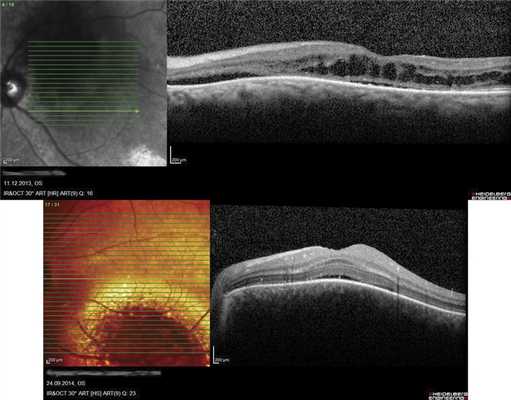

Как показывают наши наблюдения, ГХ может быть подвержена саморегрессии. Мы имели возможность наблюдать больную 66 лет, у которой в 2005 г. была выявлена ГХ проминенцией 5,5 мм (рис. 7, а). Больная отказалась от лечения и находилась под наблюдением. При контрольном исследовании спустя 9 лет по данным ОКТ и УЗИ отмечено уменьшение толщины ГХ до 1,2 мм (см. рис. 7, б-г). Очаг, по данным ОКТ, «выстоял» в сторону склеры, куполообразная проминенция в сторону сетчатки отсутствовала. Аналогичный случай описан M. Munteanu и соавт. в 2013 г. [17].

Рис. 7. Офтальмоскопическая картина глазного дна при саморегрессии ГХ (в) и соответствующие данные УЗИ в динамике (а - на момент выявления ГХ; б - при контрольном обследовании через 9 лет) и результат ОКТ (г) (красными стрелками отмечена область изменений в хориоидее, желтыми - в сетчатке).